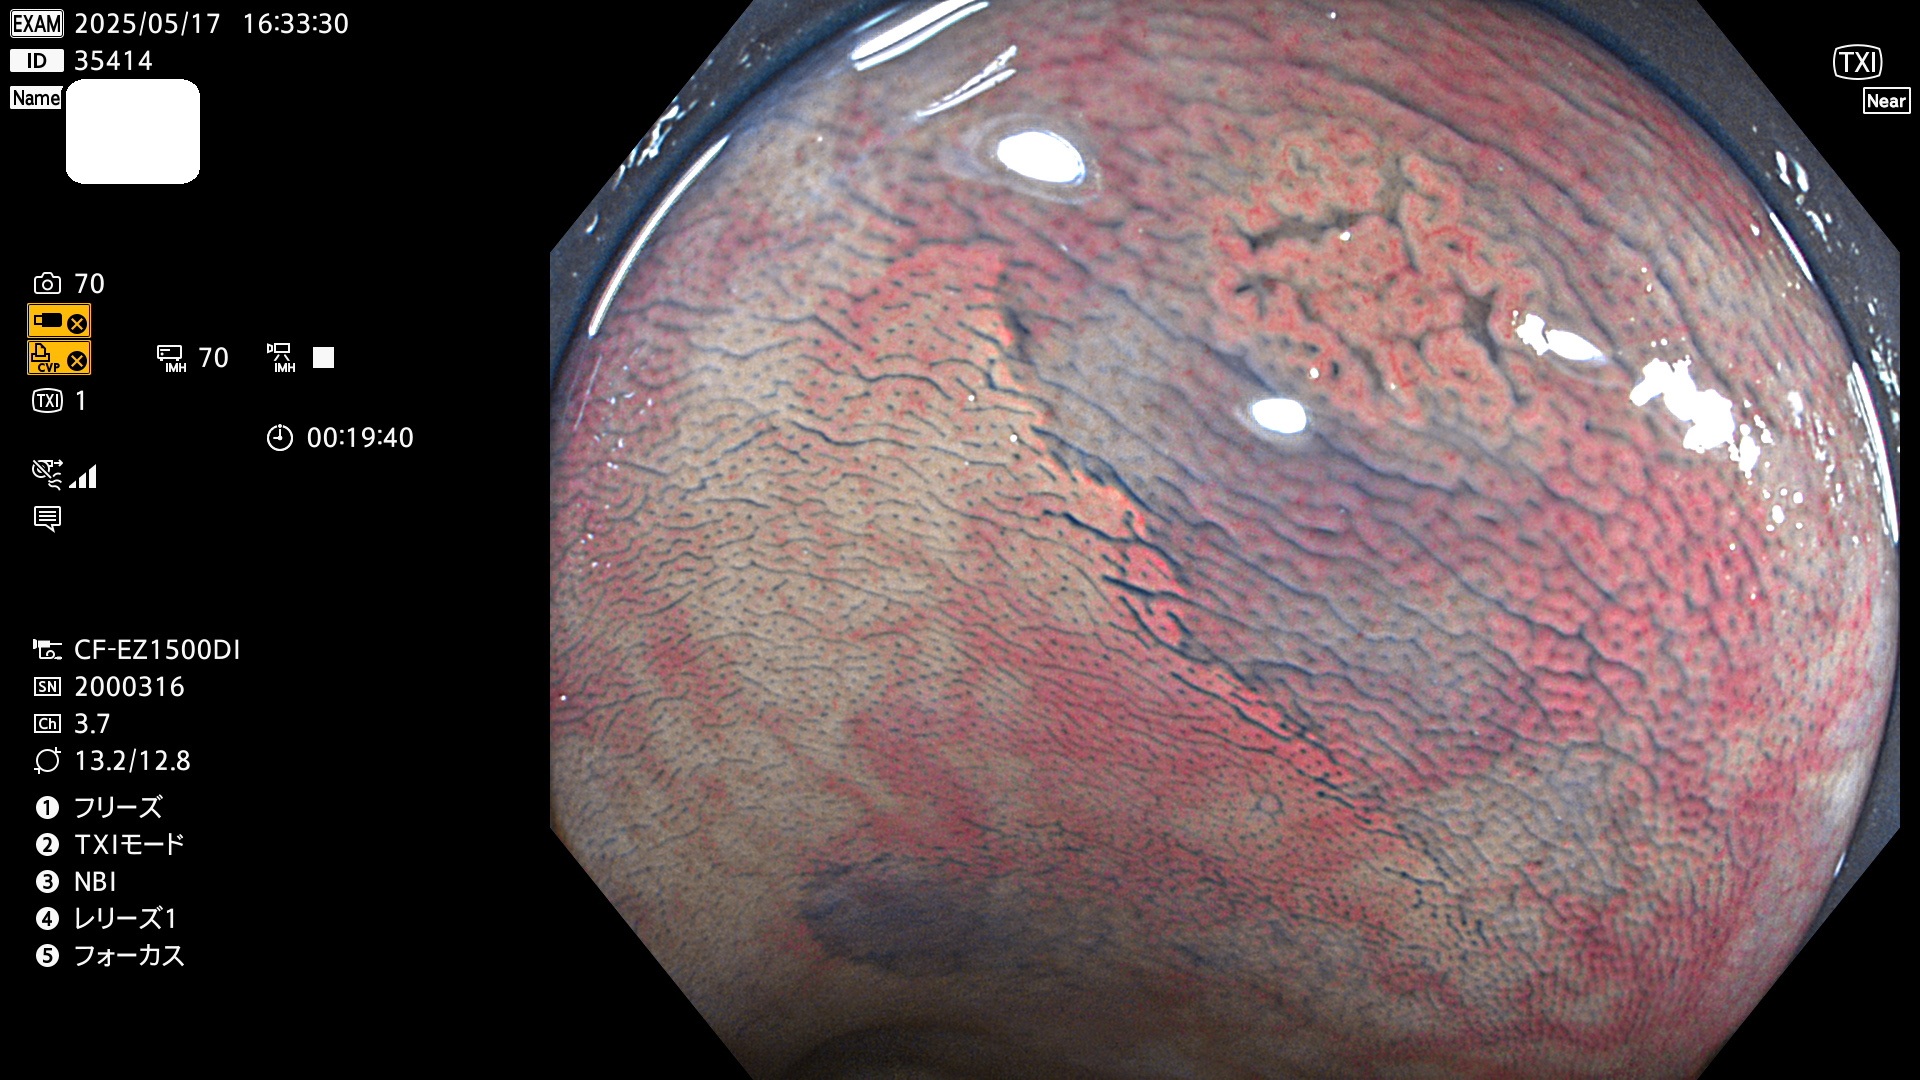

今週のUb、Uc型腺腫

完全に平坦な物をUb、陥凹している物をUcと呼びます。Ubは認識が困難で、Ucはびらん(炎症)と紛らわしいために見落とされやすく、「内視鏡後・大腸癌」の原因になります。

抽出の対象期間 2025年5月15日〜5月18日の4日間(48件の検査)6個 (6/48=13%)